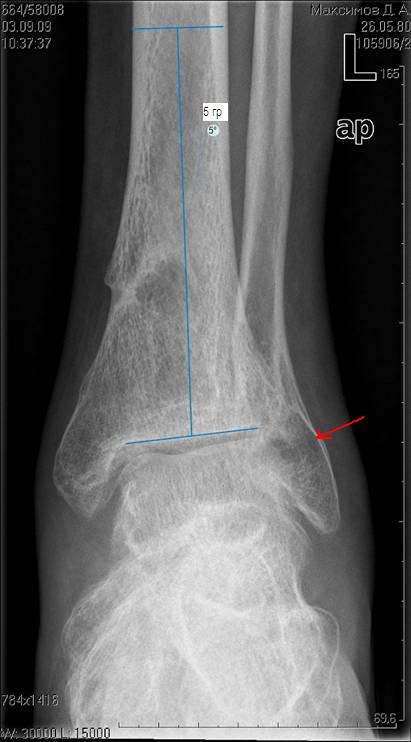

[Ortho] три картинки к моему сообщению "очередной посттравматический артроз голеностопного сустава)

Имя     : прямая проекция1.JPG

Тип     : image/jpeg

Размер  : 35655 байтов

Описание: отсутствует

Url     : http://weborto.net:8080/pipermail/ortho/attachments/20090903/35ba3f6d/attachment-0002.jpeg